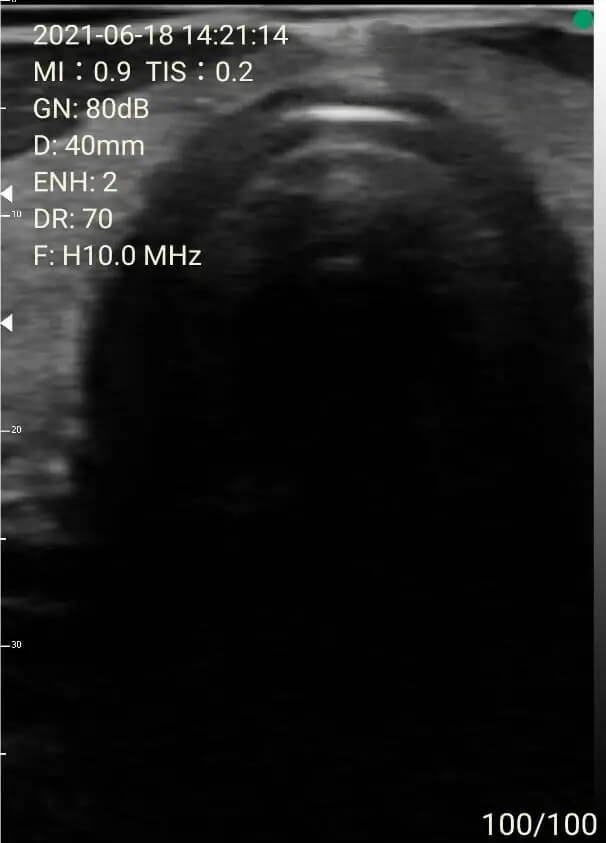

1. Thyroid survey

Thyroid and common carotid artery in B mode and with color doppler.

Thyroid isthmus and trachea.

Sagittal view of the thyroid gland.

Images of thyoid scan on a 35-year-old healthy man.